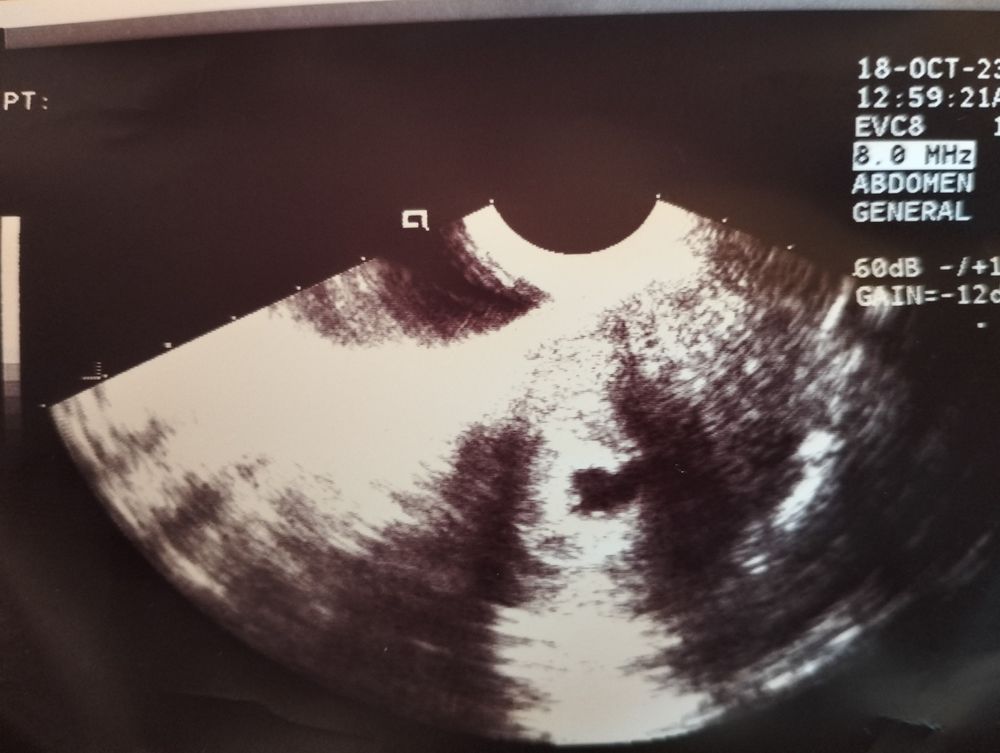

Был один малыш,а теперь двойня

Изображение Изображение Sabedoria,ну если смотреть по сниму то их двое в одном месте,хотя может срок маленький ещё и ничего толком не ясно🥰

Алина Петрова, я не совсем поняла где первый, а где второй?это первый? Изображение А второй вы обвели?